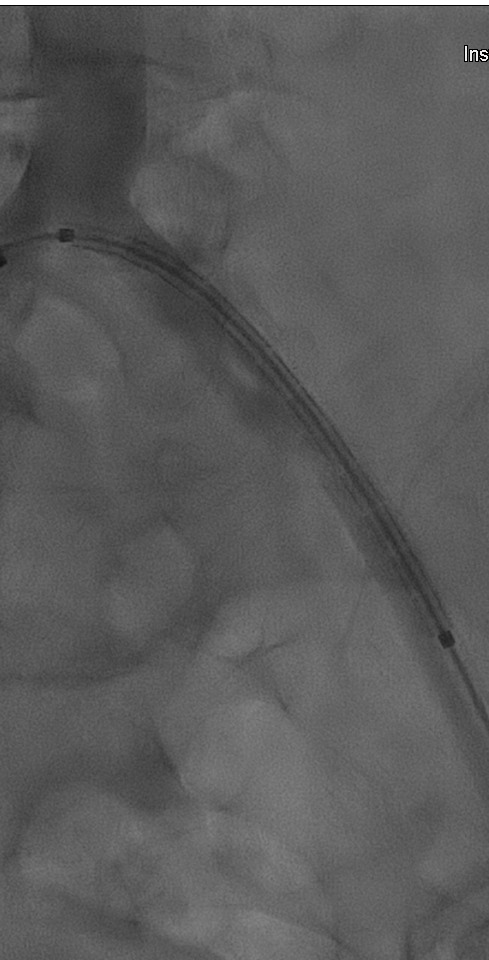

术前造影显示左髂总动脉起始部闭塞,支撑导管辅助翻山成功后,用4X150mm,6X150mm球囊分别做预扩。

(术前造影及4x150mm球囊预扩)

(6x150mm球囊预扩)

预扩后造影显示管腔打开。导入8F长鞘,通过长鞘输送并植入6X100mm 的VIABAHN 支架。继续通过8F长鞘导入VBX 支架,VBX支架近端定位在髂总动脉开口处,远端重叠在VIABAHN 支架内25mm左右。通过长鞘造影判断VBX支架位置后开始释放支架。根据产品外包装提示,当压力泵压力在6atm时,VBX 支架直径为7.1mm,此时支架会完全展开。故第一次加压6atm,支架顺利展开后排空并回撤球囊。调整球囊位置避开支架重叠区,在髂总动脉开口处再次给球囊加压到11atm,观察到支架直径随球囊的增大发生了扩张。根据产品信息提示此时已到达目标直径8mm。撤出球囊后在腹主动脉做整体造影,髂动脉开通良好。但发现VBX 支架近端与左侧腹主动脉分叉处贴壁不完全,判断是由于球囊后扩张是翻山的形式,使支架跟随了球囊的形态导致,故左侧股动脉入路上8mm直径的球囊在VBX开口处进行贴壁性后扩。支架形态被成功纠正,贴壁良好。